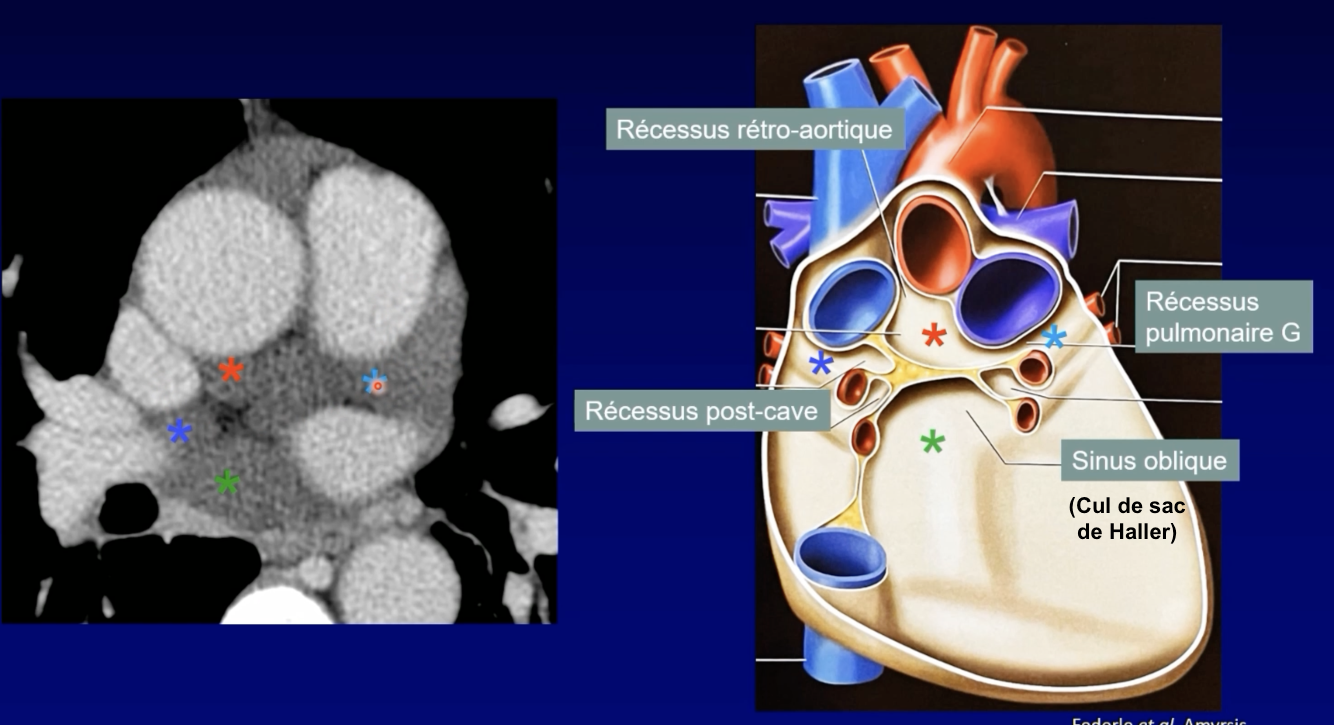

Schema

Récessus Aortique supérieur

Sinus Transverse

Récessus pulmonaire gauche

Sinus Oblique

Sinus Veineux Pulmonaire